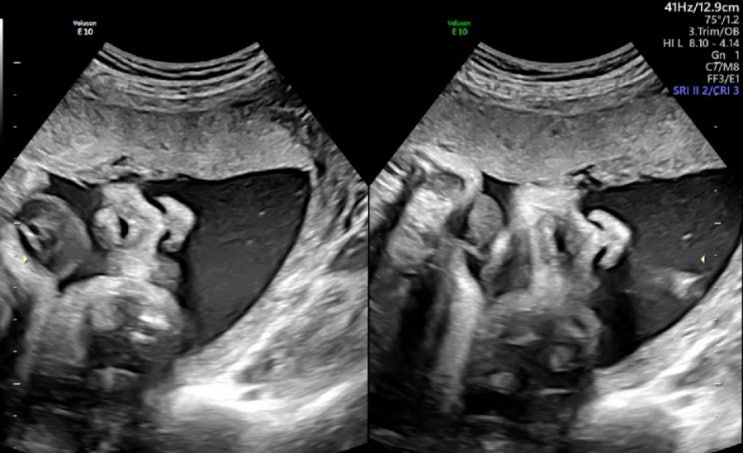

[32주 5일] 자이언트베이비가 될 상인가.

24.5.11 차 병원 검진. 역시나 나의 베이비는 다방면으로 너무 잘 크고 있다. 맘카페보면 한,두개 목록으로...

24.4.27 am8.45 임당검사 입체초음파를 서브병원에서 했고 출산 두달 남기고 본격적으로 차병원으로 전원. ...